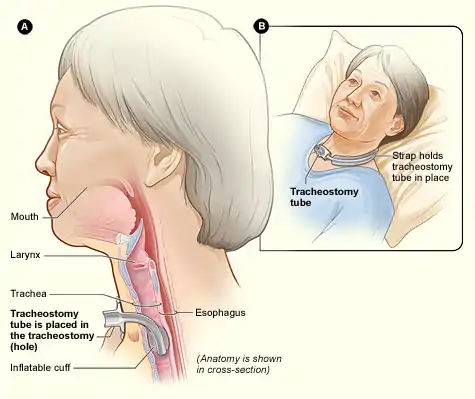

Tracheotomy (/ˌtreɪkiˈɒtəmi/, UK also /ˌtræki-/), or tracheostomy, is a surgical airway management procedure which consists of making an incision (cut) on the anterior aspect (front) of the neck and opening a direct airway through an incision in the trachea (windpipe). The resulting stoma (hole) can serve independently as an airway or as a site for a tracheal tube or tracheostomy tube[1] to be inserted; this tube allows a person to breathe without the use of the nose or mouth.

Components

A tracheostomy tube may be single or dual lumen, and also cuffed or uncuffed. A dual lumen tracheostomy tube consists of an outer cannula or main shaft, an inner cannula, and an obturator. The obturator is used when inserting the tracheostomy tube to guide the placement of the outer cannula and is removed once the outer cannula is in place. The outer cannula remains in place but, because of the buildup of secretions, there is an inner cannula that may be removed for cleaning after use or it may be replaced. Single-lumen tracheostomy tubes do not have a removable inner cannula, suitable for narrower airways. Cuffed tracheostomy tubes have inflatable balloons at the end of the tube to secure them in place. A tracheostomy tube may be fenestrated with one or several holes to let air through the larynx, allowing speech.[8]

The typical procedure done is the open surgical tracheotomy (OST) and is usually done in a sterile operating room. The optimal patient position involves a cushion under the shoulders to extend the neck. Commonly a transverse (horizontal) incision is made two fingerbreadths above the suprasternal notch. Alternatively, a vertical incision can be made in the midline of the neck from the thyroid cartilage to just above the suprasternal notch. Skin, subcutaneous tissue, and strap muscles (a specific group of neck muscles) are retracted aside to expose the thyroid isthmus, which can be cut or retracted upwards. After proper identification of the cricoid cartilage and placement of a tracheal hook to steady the trachea and pull it forward, the trachea is cut open, either through the space between cartilage rings or vertically across multiple rings (cruciate incision). Occasionally a section of a tracheal cartilage ring may be removed to make insertion of the tube easier. Once the incision is made, a properly sized tube is inserted. The tube is connected to a ventilator and adequate ventilation and oxygenation is confirmed. The tracheotomy apparatus is then attached to the neck with tracheotomy ties, skin sutures, or both.[11][12]